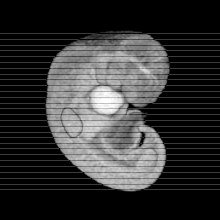

MRI Slice Selector

Mouse: click on a line below to select a view

Finger: tap a line below with a very light touch